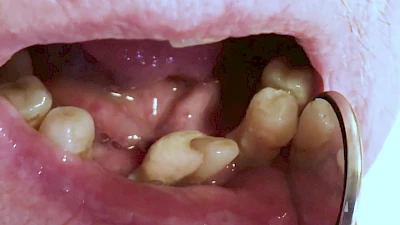

Eine geringe spürbare Beweglichkeit der Zähne ist durchaus normal, da Zähne über Fasern im Kieferknochen aufgehängt sind. Lassen sich Zähne, Kronen oder Brücken jedoch deutlich sichtbar bewegen, besteht die Gefahr, dass sie sich lösen und verschluckt oder aspiriert werden. Deshalb sollte in diesen Fällen der Zahnarzt verständigt werden.